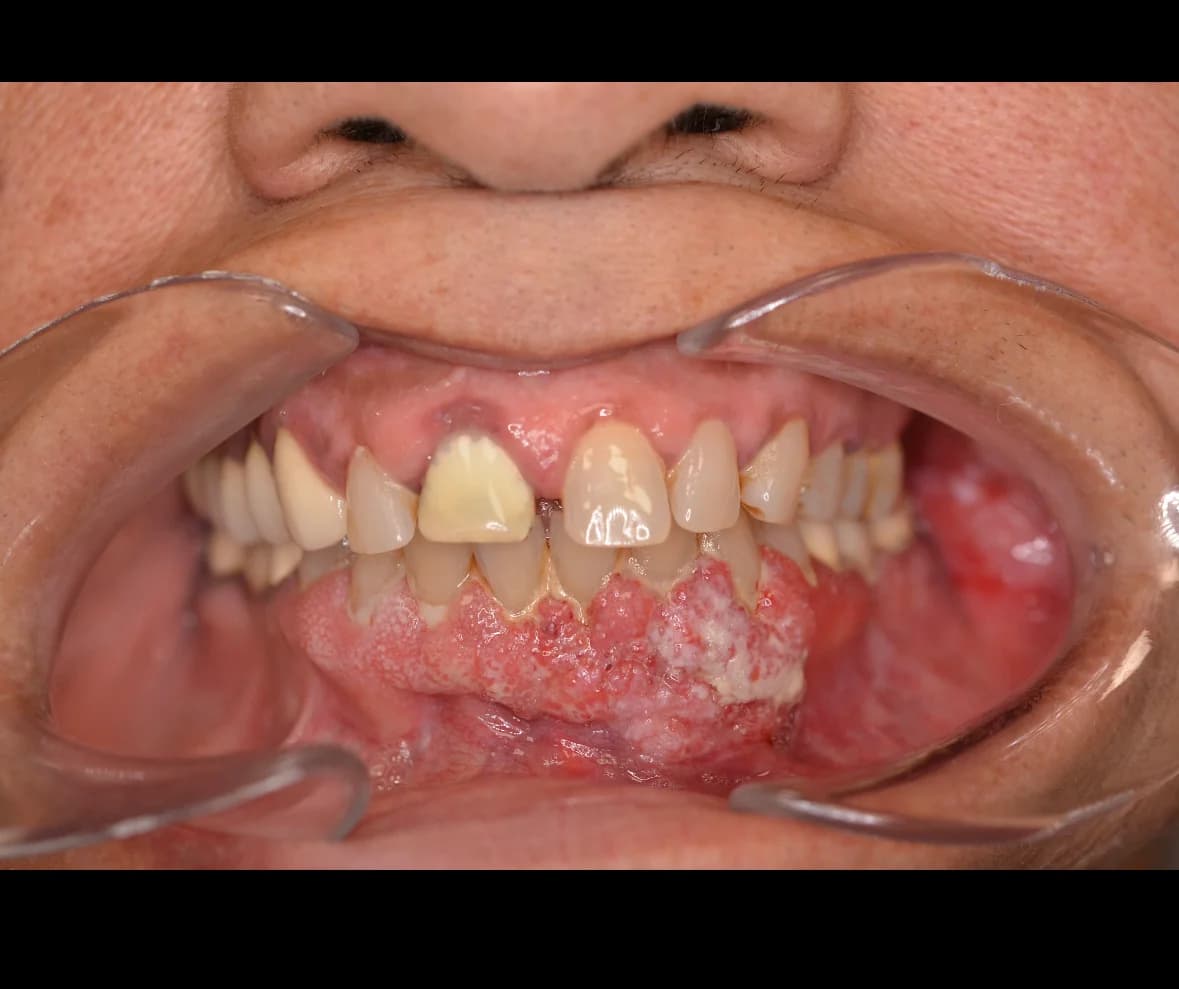

The oral and maxillofacial surgeon plays an essential role in treating oral pathologies, which can include a wide range of conditions affecting the tissues and structures of the mouth, jaw, and face. These pathologies can range from benign tumours to aggressive tumours and even malignant tumours. Early detection and management of certain conditions can have a significant impact on recovery and long-term prognosis. It may happen during a consultation with your dentist or family doctor that they notice an abnormality and are concerned about its nature. They will then send a consultation request for one of the surgeons on our team to examine you. After a thorough evaluation of the different structures of the face, oral cavity, jaws, and neck, and in some cases, taking x-rays, a biopsy may be necessary. A biopsy involves taking a tissue sample that is submitted for microscopic analysis by a pathologist. This can then help establish a treatment plan ranging from simple regular follow-ups to surgical treatment.